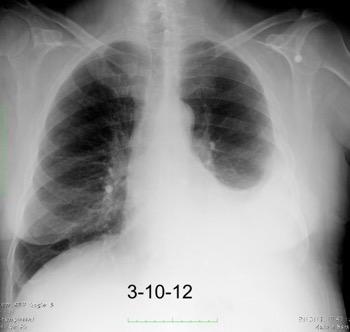

Tb con paquipleuritis calcificada, Hidroneumotórax. Cavidad apical conectada a pleura. Atelectasia redonda

Eyler WR et l. Rib enlargement in patients with chronic pleural disease . AJR 1996